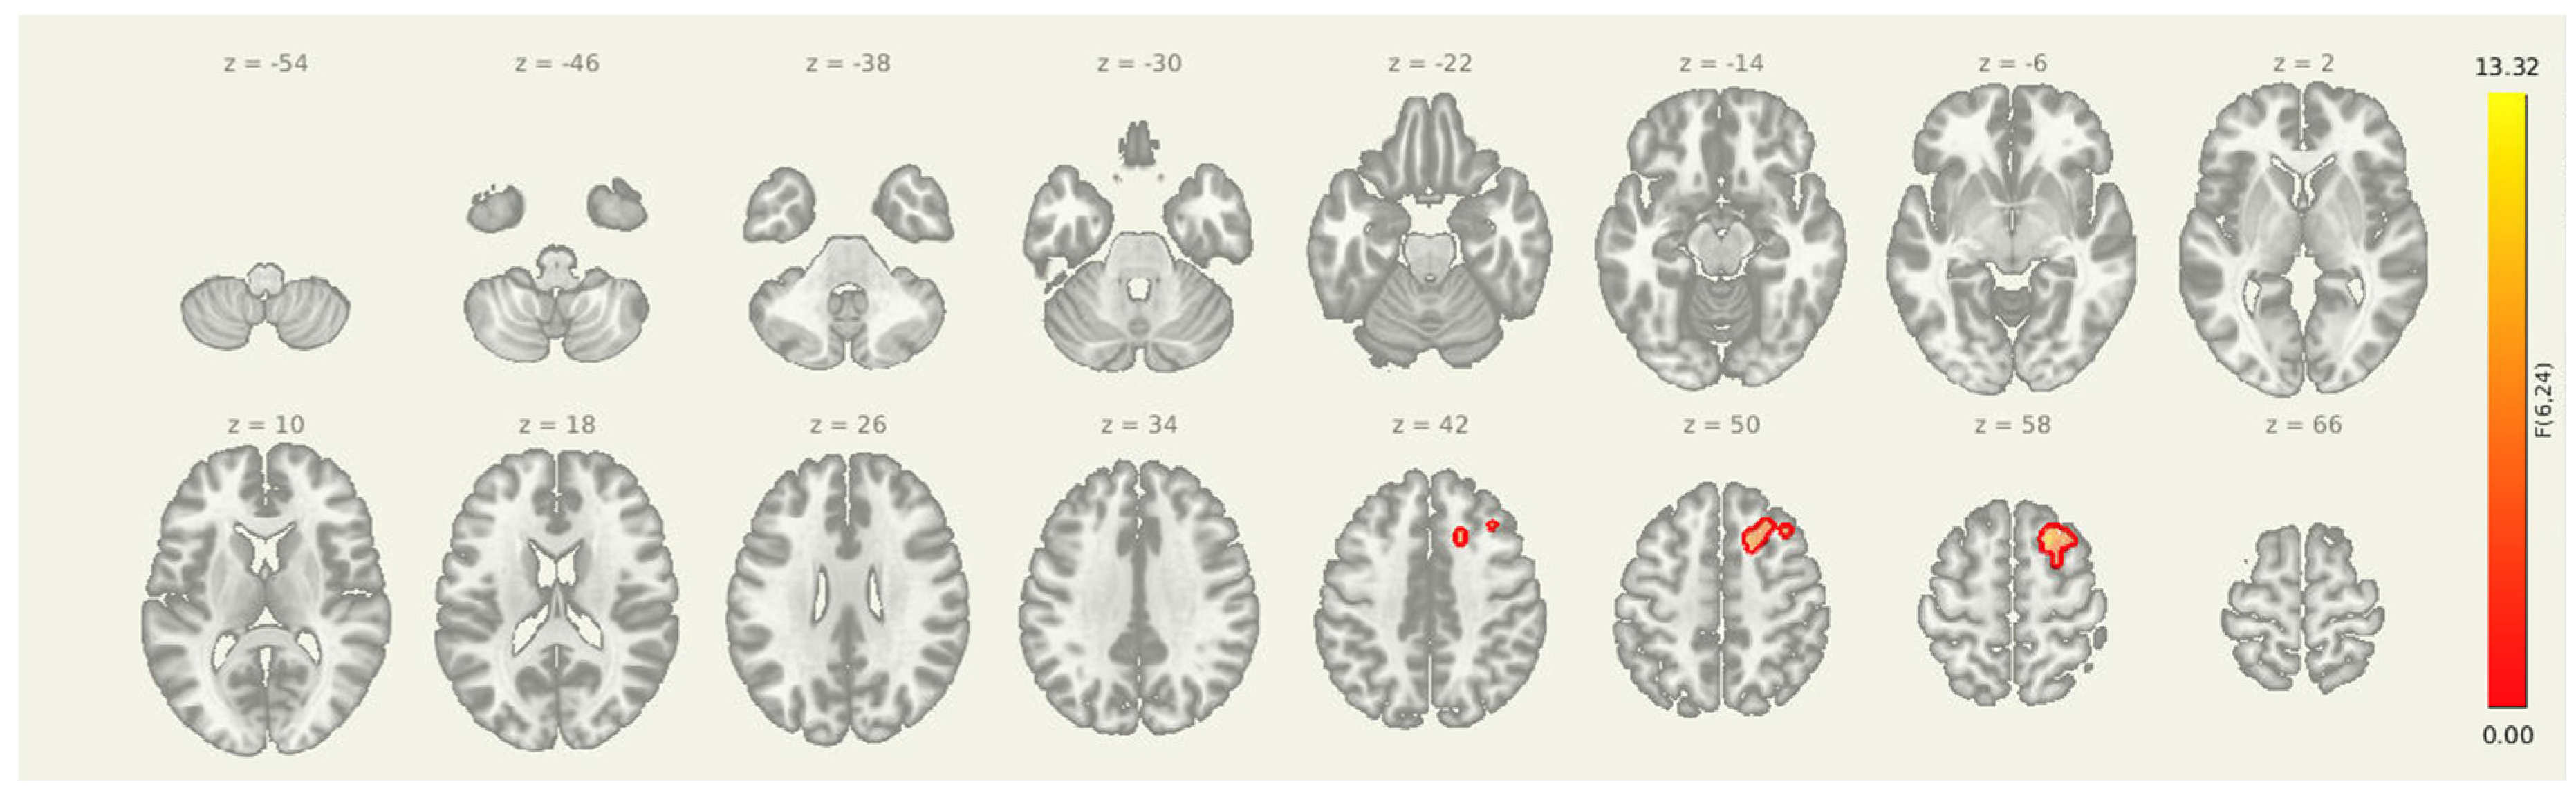

Following the intervention, seed-to-voxel analysis revealed significantly greater amygdala connectivity at the pre-intervention timepoint compared to post-intervention in two clusters. The first was located in the left postcentral gyrus and somatosensory association area (MNI: +06, -38, +34; cluster size = 382 voxels; p-FDR = 0.0107), and the second was centered in the right superior frontal gyrus (MNI: +22, +22, +54; cluster size = 315 voxels; p-FDR = 0.0171). These results suggest a reduction in amygdala coupling with both sensorimotor and prefrontal regions after the combined rTMS and exercise intervention, consistent with decreased engagement of limbic-driven pain and vigilance networks.

Figure 3. Seed-to-voxel connectivity reductions from the amygdala following intervention. Significant clusters reflect greater connectivity at pre-intervention compared to post-intervention (PRE > POST), including regions in the left postcentral gyrus and right superior frontal gyrus. Results are thresholded at p-FDR < 0.05 and shown in MNI space.

51. Cluster (MNI x, y, z) 52. Size (voxels) 53. p-FWE 54. p-FDR 55. Location

56. +06, -38, +34 57. 382 58. 0.010472 59. 0.010656 60. Left Postcentral Gyrus (BA 1/2)

61. +22, +22, +54 62. 315 63. 0.033151 64. 0.017062 65. Right Superior Frontal Gyrus (BA 8)